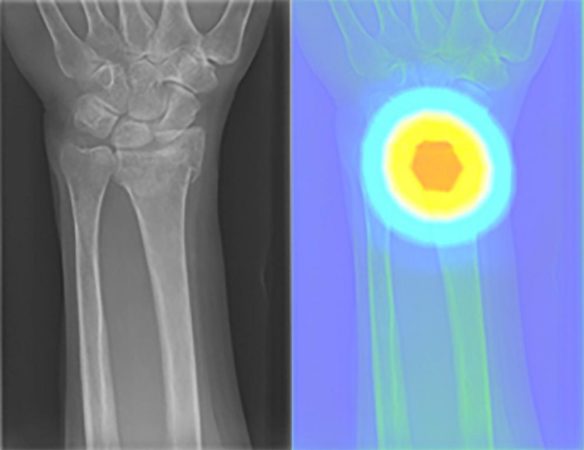

In einem ersten Projekt arbeiten die Radiolog*innen gemeinsam mit Expert*innen des Instituts für Genetische Epidemiologie des Universitätsklinikums Freiburg daran, Nierenerkrankungen anhand von magnetresonanztomografischen (MRT) Bildern frühzeitig zu erkennen. Ein weiterer Schwerpunkt des Supercomputers ist die Analyse von Röntgenbildern bei möglichen Knochenbrüchen. Dabei ist es entscheidend die Ergebnisse der KI-Software überprüfen zu können. Dafür legt die Software eine sogenannte Heatmap über das Röntgenbild und hebt so farblich hervor, wo sie den Knochenbruch erkannt hat.